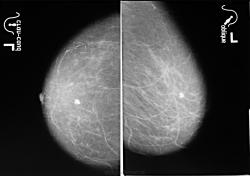

Тут помимо основного узла или даже лучше сказать узлов имеются вторичные инфильтративно-отечные изменения молочной железы с переходом в аксиллярную область. Любопытно, а нет ли в ребрах изменений Печальный случай...

Уважаемые коллеги! А с чем в 2008г отправляли к онкологам? Кальцинат в центральном отделе железы опасения не вызывает, а судя по снимкам 2010г, опухоль исходит из нижневнутреннего квадранта, в 2008 г либо этот участок не захвачен в поле съемки, либо опухоль развилась позже, так называемый "интервальный рак", быстро растущий, развившися после очередного профилактического исследования.

Извините за отсутствие маркировки. Но это просто здоровая железа, а не 2008 год. Снимки за 2008 отсутствуют ("где то потеряла")